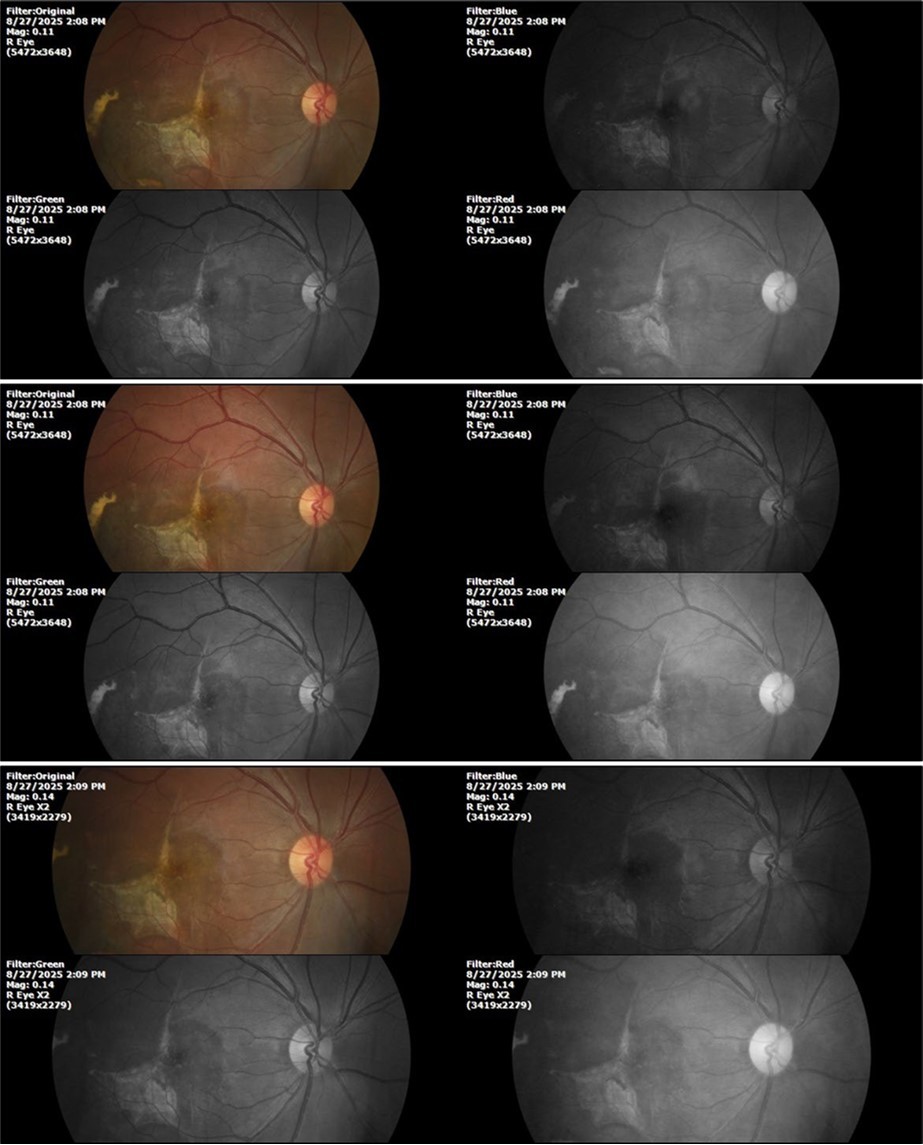

August 26, 2025

It's been fine, there's only a little veil that prevents it from seeing well completely, although it's very transparent (Figure 31, Figure 32, Figure 33, Figure 34, Figure 35, Figure 36).

94 %

62 x ́

++/++

Figure 31.The photograph of the right eye shows an almost normal mirror reflection, as well as a better pupillary dilation.

Figure 32.The macro photograph of the right eye shows us a cornea, anterior camera, and crystalline lens in very good condition.

Figure 33.The 3 previous photographs show that whitish mass has almost completely disappeared, and to date only a remnant remains on the left side of the photograph. The chorioretinal scar that is now observed corresponds to the area affected by the blunt trauma, which presumably caused rupture of Bruch's membrane. Fortunately, the macular region has recovered almost in its entirety, so the impairment in central vision was minimal.

Figure 8.The photograph of the superior temporal region of the retina of the right eye shows the extent of subretinal bleeding as well as retinal edema.